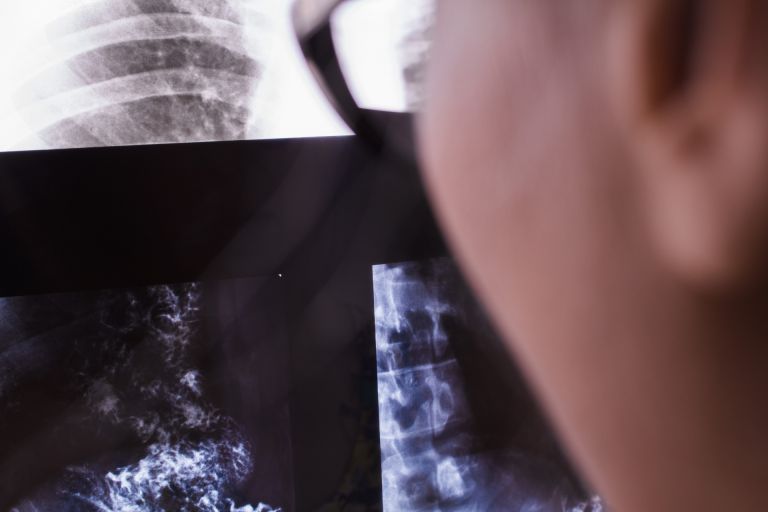

例えば、オンライン診療や事前問診の導入が進んでいる施設も増加し、デジタル化の波が医療環境にも到達していることが窺える。また、定期健康診断を中心に大規模な集団検診にも対応できる施設が集積しているのも特徴である。企業の健康経営の一端を担う健診センターは、内科診断をはじめとして血液検査、心電図、胸部レントゲン撮影といった多様なサービスをワンストップで提供している。検診後のフォローアップも丁寧に行われており、予防医療の観点からも高い評価を受けている。エリア内の内科や病院に勤めるスタッフは、多様な年齢層・多忙なライフスタイルに合わせてきめ細かな診療体制を心掛けている。